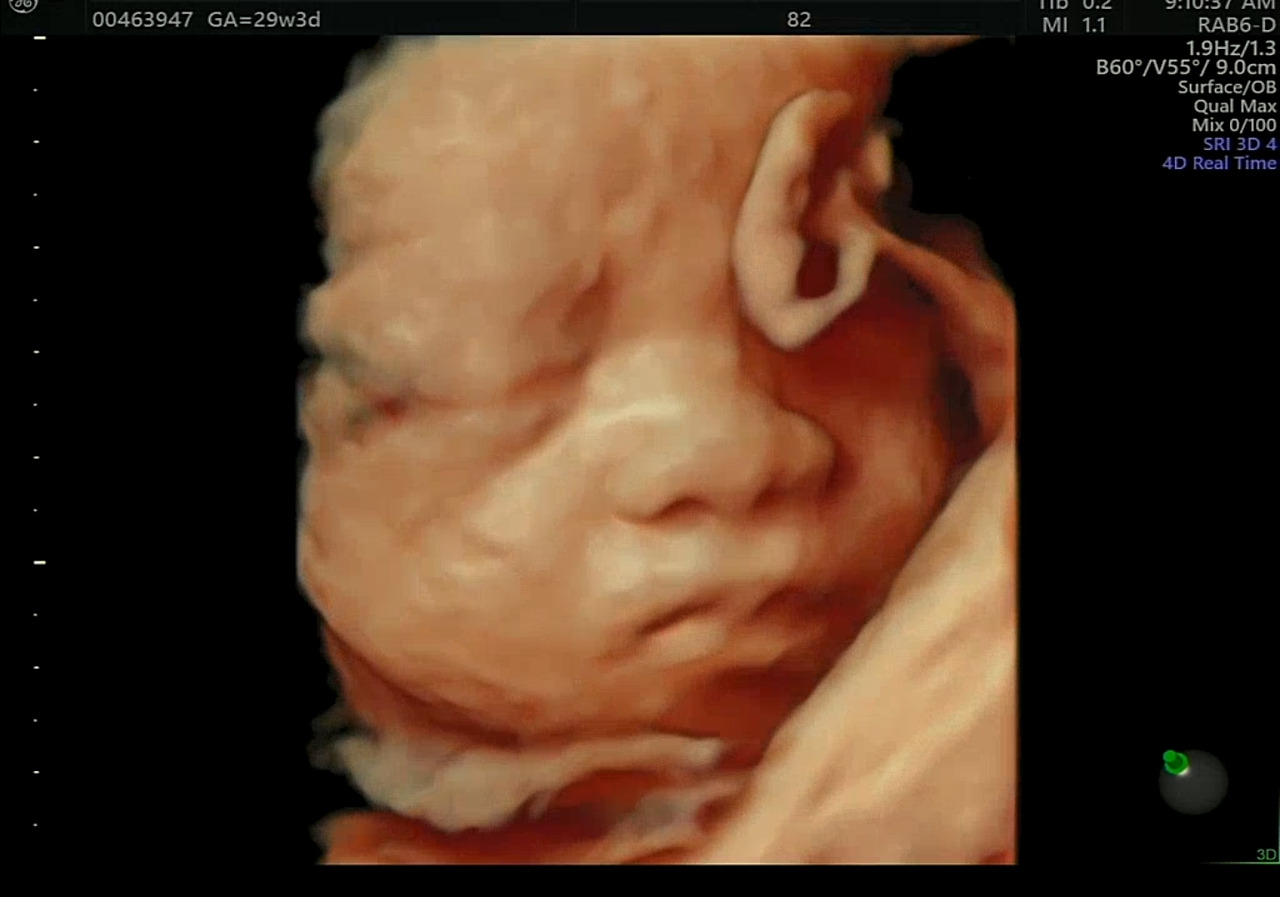

29주 : 입체초음파

초음파가 태아에 안 좋다는 것을 알고 있었지만 아기의 얼굴을 볼 수 있는 입체초음파는 기다리지 않을 수 없었다.

아기의 얼굴을 미리 보면 모성애가 생겨서 막달 우울증도 이겨낼 수 있다고 한다.

눈코입 아기얼굴을 보니, 임신기간 내내 걱정이 많았었는데 왠지 안도감이 느껴졌다. 그리고 29주가 됐으니, 당장 태어나도 생존확률이 높다는 생각에 걱정을 한시름 놓게 되었다.